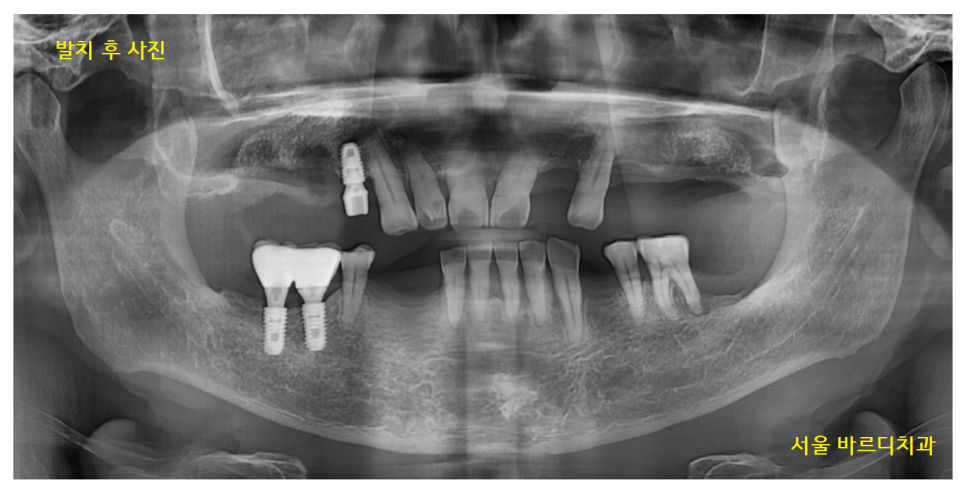

23.02.18

뽑을 거 뽑고

살릴 거 살려서

정리를 1차 완료한 사진입니다.

전반적으로 남아있는 잇몸뼈가 없어서

철저한 디지털 분석이 필요했습니다.